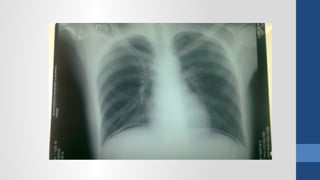

2. Ch n đoán hình nhẩ ả

Xquang b ng đ ng không chu n bụ ứ ẩ ị

2. Ch nđoán hình nhẩ ả Siêu âm Xquang b ng đ ng không chu n bụ ứ ẩ ị CT Scanner N i soi thăm dòộ

• #64 Xquang - Viêm phổi (thâm nhiễm phổi), - Tắc ruột (mức nước hơi), - Thủng tạng rỗng (hơi tự do trong bụng), - Sỏi thận và hệ niệu (vôi hóa bất thường), - Viêm RT (fecalith)?, - Thoát vị kẹt (ruột trồi khỏi giới hạn ổ bụng)?, - Nhồi máu mạc treo (hơi trong TM cửa), - Viêm tụy mãn (vôi hóa tụy), - Viêm tụy cấp (sentinel loop, colon cutoff), - Phình ĐM (bờ vôi hóa)?, - Tụ máu hoặc áp xe sau phúc mạc (mất bóng cơ psoas), Siêu âm - Những bệnh vùng chậu (u buồng trứng, Viêm RT cấp, thai ngoài tử cung, thai trong tử cung), - Sỏi mật (túi mật, đường mật), - Gan (áp xe, bướu gan), - Thận (ứ nước, sỏi), - Dịch tự do trong bụng (xuất huyết nội, dịch viêm, ascites) CT Scan: - có giá trị định bệnh cao hơn SA nhưng không nên dùng cho BN nữ đang mang thai hoặc cho trẻ em. - Viêm đại tràng thiếu máu (dấu ấn ngón tay trên thành đại tràng). &amp;lt;number&amp;gt;